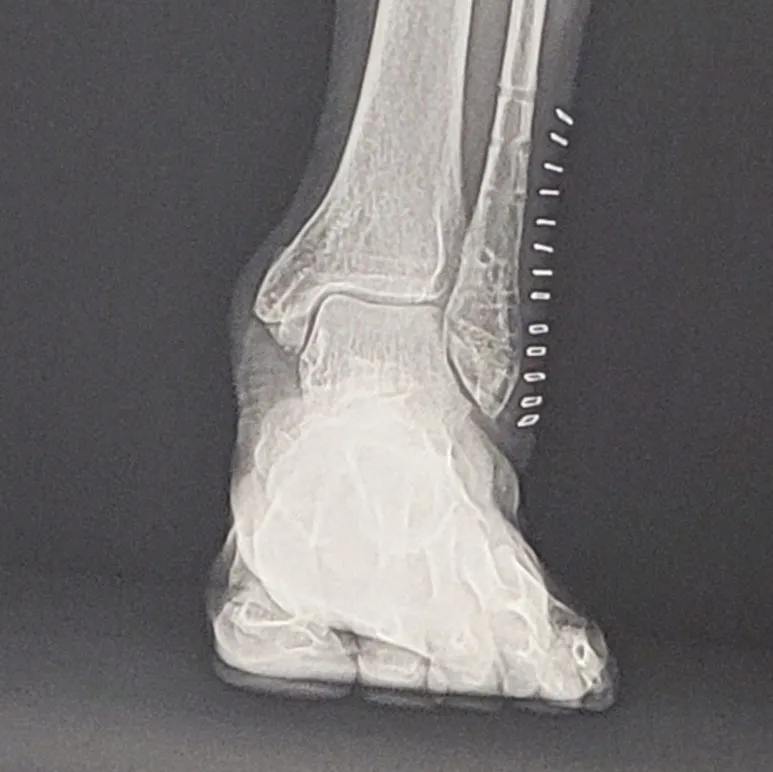

SE-06cc31b0-59af-41a4-90ce-619d87fe5884.jpg?type=w773 발목 골절 후 1,2차 수술 후 마지막 스테일플러스, 실밥 제거 전

드디어 몸에 있는 철(1차 수술 핀 삽입, 2차 수술에서 핀 제거, 꿰매면서 발목 바깥쪽 스테이플러스 13개, 발목 안쪽 실밥 제거)을 모두 제거하고 실밥도 제거했다. 뼈는 잘 붙었다니 다행이다.